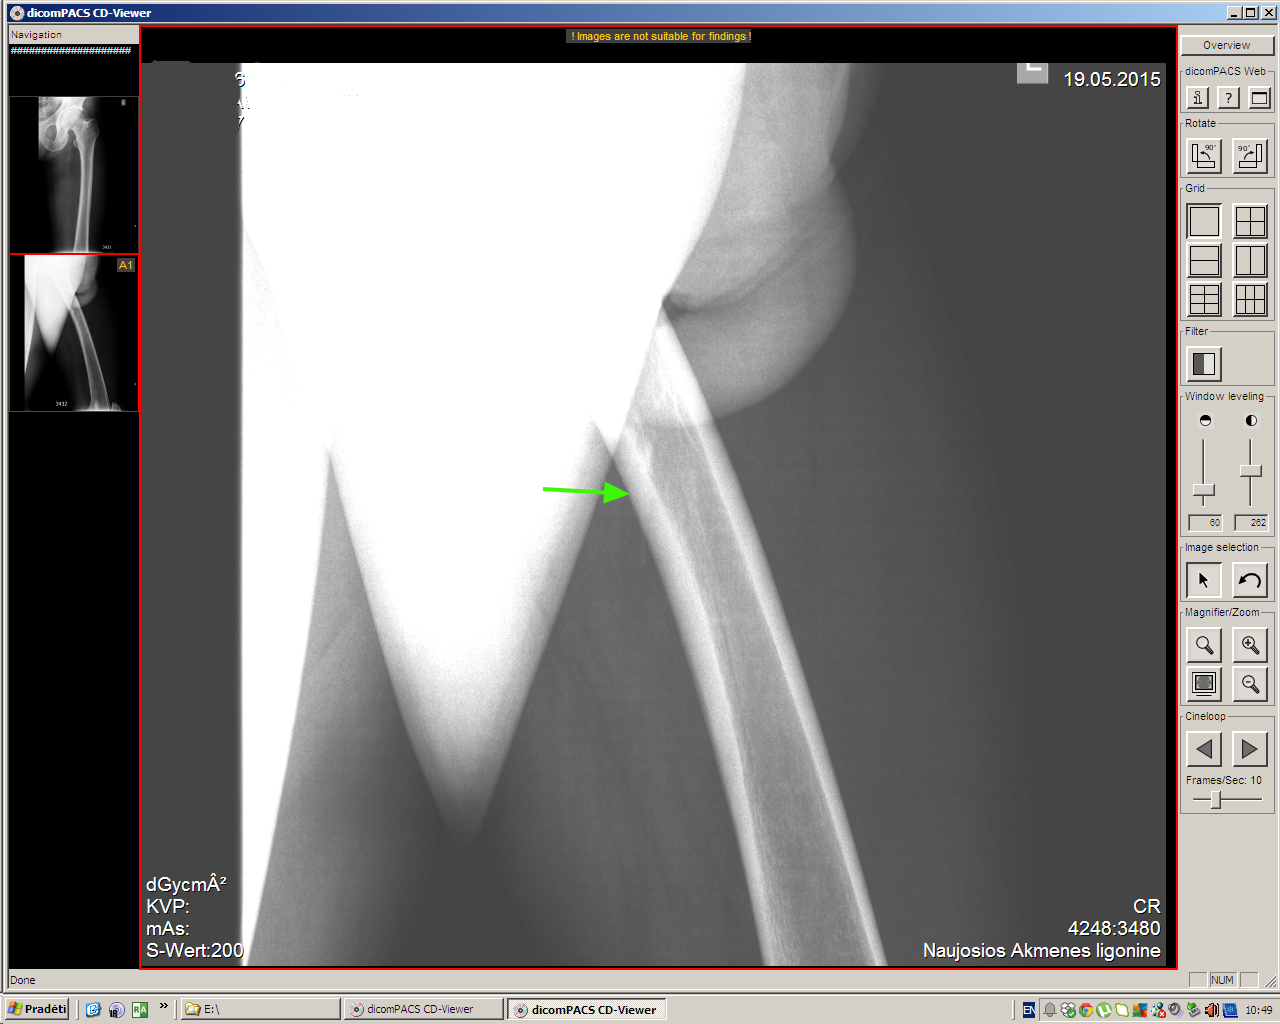

Молодой мужчина, деревенский житель, обратился к доктору по поводу образования на передней поверхности бедра, тот отправил на рентген (патологии не обнаружено), а затем УЗИ.

Травму пациент отрицает.

Ультразвуковое исследование здесь было более информативным, чем обычный рентген, хотя если присмотреться, то и на рентгеновском снимке шип можно увидеть.